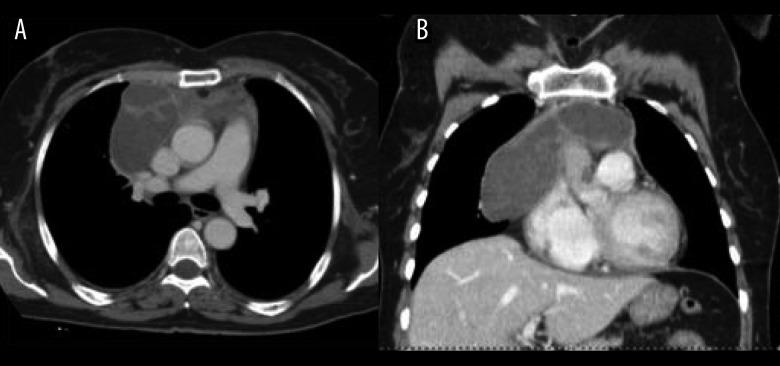

A 60-year-old woman with recent chest pain and no history of previous disease was admitted to our departement to investigate the result of a previous chest X-ray that showed bilateral mediastinal enlargement; for this purpose, enhanced chest CT scan was performed using a 64-rows scanner (Toshiba, Aquilion 64, Japan) before and after intravenous bolus administration of iodinated non ionic contrast agent; CT images demonstrated the presence of a large mediastinal mass (11×8 cm) located in the anterior mediastinum who extended from the anonymous vein to the cardio-phrenic space, compressing the left atrium and causing medium lobe atelectasis; bilateral pleural effusion was also present.

一名60岁女性,近期出现胸痛,既往无疾病史,因之前胸部X线显示双侧纵隔增宽而入住我院进行进一步检查;为此,在静脉推注碘化非离子型造影剂前后,使用64排螺旋CT扫描仪(日本东芝Aquilion 64)进行了增强胸部CT扫描;CT图像显示前纵隔有一个巨大纵隔肿块(11×8 cm),从无名静脉延伸至心膈角区,压迫左心房并导致中叶肺不张;同时还存在双侧胸腔积液。